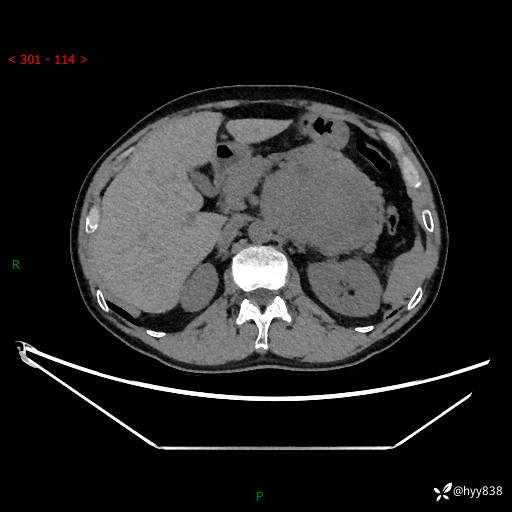

年龄:61岁

主诉:发现腹膜后肿瘤3天

腹部CT平扫+增强(动脉期+静脉期)